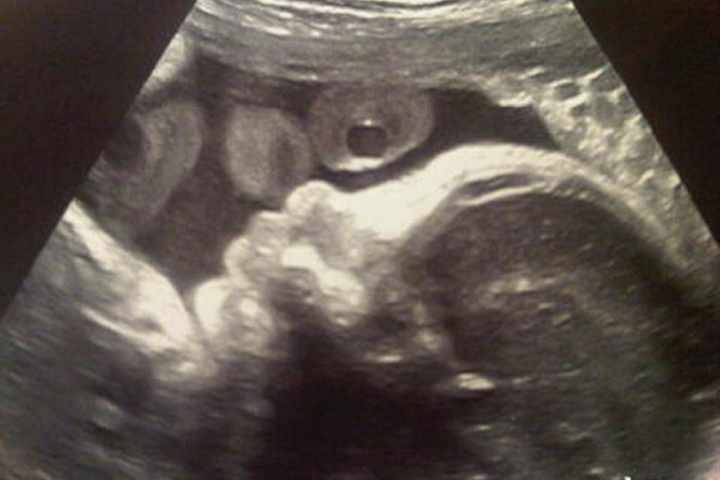

NOTICIAS 06/12/2012Dan a conocer la primera imagen del bebé de Shakira y PiquéLa cantante Shakira se prepara para ser mamá para enero del próximo año y, como en otras oportunidades, compartió su alegría con sus seguidores en Twitter.

Esta vez la cantante subió una imagen de su bebé de la última ecografía que se realizó, transitando siete meses y medio de embarazo.